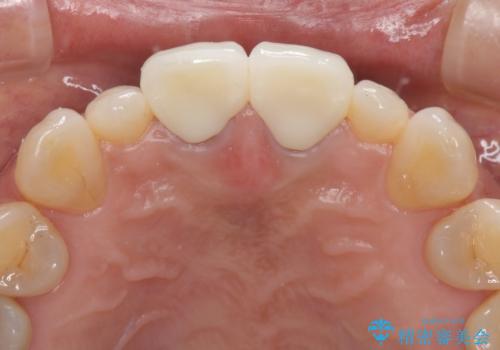

前歯をメタルフリーに 根管治療で不安を取り除いてから

セラミック治療と根管治療を行いました。

金属を使用したメタルボンドクラウンが入っていたため、いつかオールセラミックにしたいときに根管治療も行ったほうが良いとご提案し、今回行いました。

歯と歯肉の境目の色は、歯自体が黒くなっている場合、完全にカバーすることは難しいです。